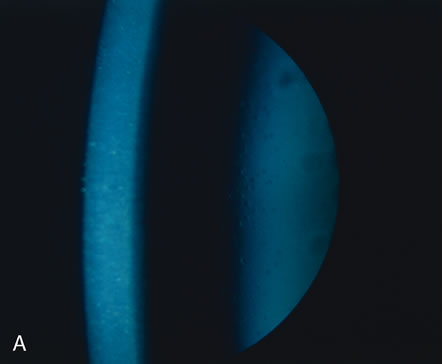

Granular corneal dystrophy is a primary abnormality of the stroma leading to sharply demarcated deposits of nonspecific, hyaline material.147 The hyaline deposits appear to be composed of keratoepithelin or BIGH3 protein.140,148 The intervening cornea stroma remains transparent, potentially allowing good vision (Figs. 29, 30, and 31).

Fig. 30. Granular dystrophy. A. Note the clear cornea between the stromal granules. B. Granules stain deeply with hematoxylin-eosin stain. C. Granules seen by light microscopy (inset) are shown by electron microscopy to consist of dense granules. Many granules are “apertured.” D. Close relationship of dense and apertured granules to packed, “folded” macromolecules (“filaments”). The latter are believed to be precursors of granule formation. Inset shows Congo red positivity at the periphery of the granule. (Courtesy of SEI Photoarchives.)

Fig. 31. Granular dystrophy. A. Clinical appearance. Biopsy (inset) shows the presence of a typical stromal granule (arrow). B. Granular dystrophy recurred in full-thickness grafts several years later. The granules (arrow) are seen by side illumination. Biopsy (inset) shows a new lesion within the graft. A typical collection of granular material (arrow) lies within the stroma beneath Bowman's membrane (bm).C. These granules from a biopsy are typical of granular dystrophy. BL, Bowman's layer. (Courtesy of SEI Photoarchives.) (Brownstein S, Fine BS, Sherman ME et al: Granular dystrophy of the cornea—light and electron microscopic confirmation of recurrence in a graft. Am J Ophthalmol 77:701, 1974.)